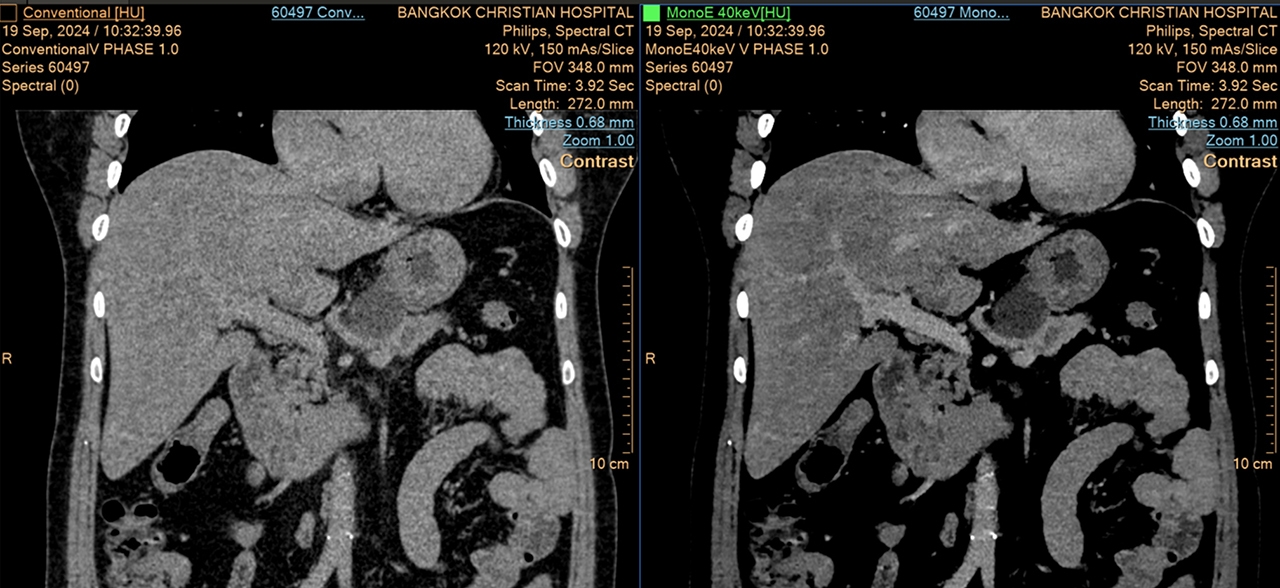

ความสามารถในการปรับความเข้มของสารทึบรังสีในภาพ ทำให้แพทย์สามารถเห็นความแตกต่างระหว่างเนื้อเยื่อปกติกับรอยโรคได้อย่างชัดเจน สิ่งที่พิเศษยิ่งกว่านั้นคือแพทย์สามารถใช้สารทึบรังสีในปริมาณที่น้อยลง ซึ่งถือเป็นประโยชน์อย่างยิ่งสำหรับผู้ป่วยโรคไตและเด็กๆ ที่ต้องระมัดระวังเรื่องสารเหล่านี้เป็นพิเศษ

(ซ้าย: ภาพ CT ทั่วไป / ขวา: ภาพ Spectral CT)